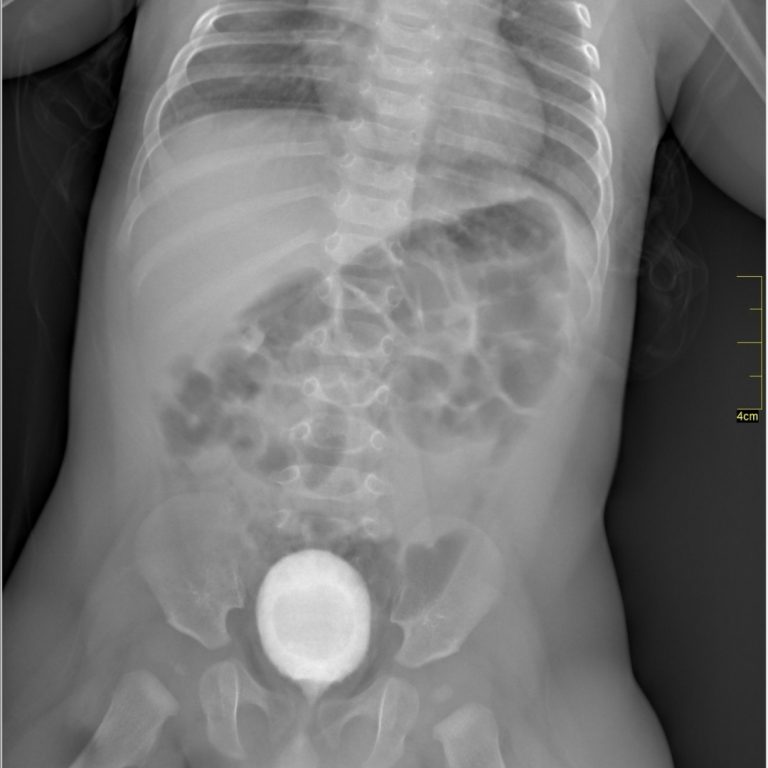

VOİDİNG SİSTOGRAFİ

Voiding Sistoüretrografi (VSUG) mesane ve alt üriner sistemin değerlendirilmesi için kullanılan bir X-ışını ile görüntüleme yöntemi olup mesaneye bir sonda ile verilen kontrast madde aracılığıyla, işeme sırasında idrar yollarının görüntülenmesidir.Çocuklarda üriner sistem infeksiyonunu takiben vezikoüreteral reflü şüphesi varlığında VSUG incelemesine gerek duyulmaktadır.

Voiding sistoüretrografi nasıl yapılır ?

Radyoloji teknisyeni çocuğunuzu inceleme masasına yerleştirdikten sonra çocuğun hareketini engelleyici araçlar kullanabileceği gibi sizden de çocuğu tutma konusunda yardım isteyebilir. Kontrast madde verilmeden önce mesane boşken bir film çekilir. Daha sonra özel bir sıvıyla çocuğunuzun cinsel organını temizlenir ve mikropsuz bir ortam sağladıktan sonra ince bir kateter (ince, esnek bir tüp) idrar yolundan geçirerek mesaneye yerleştirilir. Tüpün ucu kontrast madde içeren bir torbaya bağlanarak yerçekiminin etkisiyle mesane tamamen dolana kadar beklenir.

Mesane dolarken mesaneden üst idrar yollarına kaçış olup olmadığına bakılarak çeşitli filmler çekilir. Mesane tamamen dolduğunda sonda çıkartılır ve çocuk idrarını yaparken seri filmler çekilir.İşeme sona erdiğinde mesanede idrar kalıp kalmadığını görebilmek için bir film daha çekilerek işlem sonlandırılır. İşlem ağrısız olmakla beraber küçük çocuklar hareketleri engellendiğinde ağlayabilmektedirler. Kateter takılmadan önce çocuğunuzun cinsel bölgesi mikroplardan arındırmak için özel bir sıvıyla temizlenir. Bu sıvı soğukluk hissi oluşturabilir. Kateterin takılması ve mesanenin kontrast madde ile doldurulması ağrısız olmakla beraber bazı çocuklar rahatsızlık hissedebilirler. Çocuğunuzun korkmaması ve sakinleşmesi için, radyasyona maruz kalabileceğinizden kurşun önlük giyme şartı ile çekim süresince yanında kalabilirsiniz. Tüm işlemler, yaklaşık 15 dakikada tamamlanır.